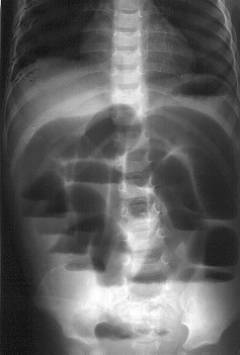

Это исследование обязательно при подозрении на заворот кишок. Метод основан на просвечивании тканей рентгеновскими лучами, что позволяет выявить наличие газа в петлях кишечника.

Обзорная рентгенограмма позволяет выявить:

- При завороте тонкого кишечника – уровень жидкости и газа в петлях выше места заворота.

- При завороте слепой кишки – увеличенное, шаровидное образование в правых отделах живота.

- При завороте сигмовидной кишки – скопление газа в ободочной кишке, что проявляется увеличением рентгенологических границ и смещением органов.

Рентгенография брюшной полости

Данное исследование необходимо при подозрении на заворот кишок. Рентгенологический метод основан на просвечивании тканей рентгеновскими лучами. Разные ткани поглощают лучи в разной степени. Воздух почти не поглощает рентгеновские лучи, поэтому его наличие в кишечных петлях легко выявить на рентгенограмме.

Обзорная рентгенограмма органов брюшной полости позволяет выявить:

- При завороте слепой кишки – увеличенное, округлое образование в правых отделах живота.

- При завороте сигмовидной кишки – скопление газа в ободочной кишке, что проявляется увеличением рентгенологических границ всех ее отделов и смещением вверх органов брюшной полости и диафрагмы.